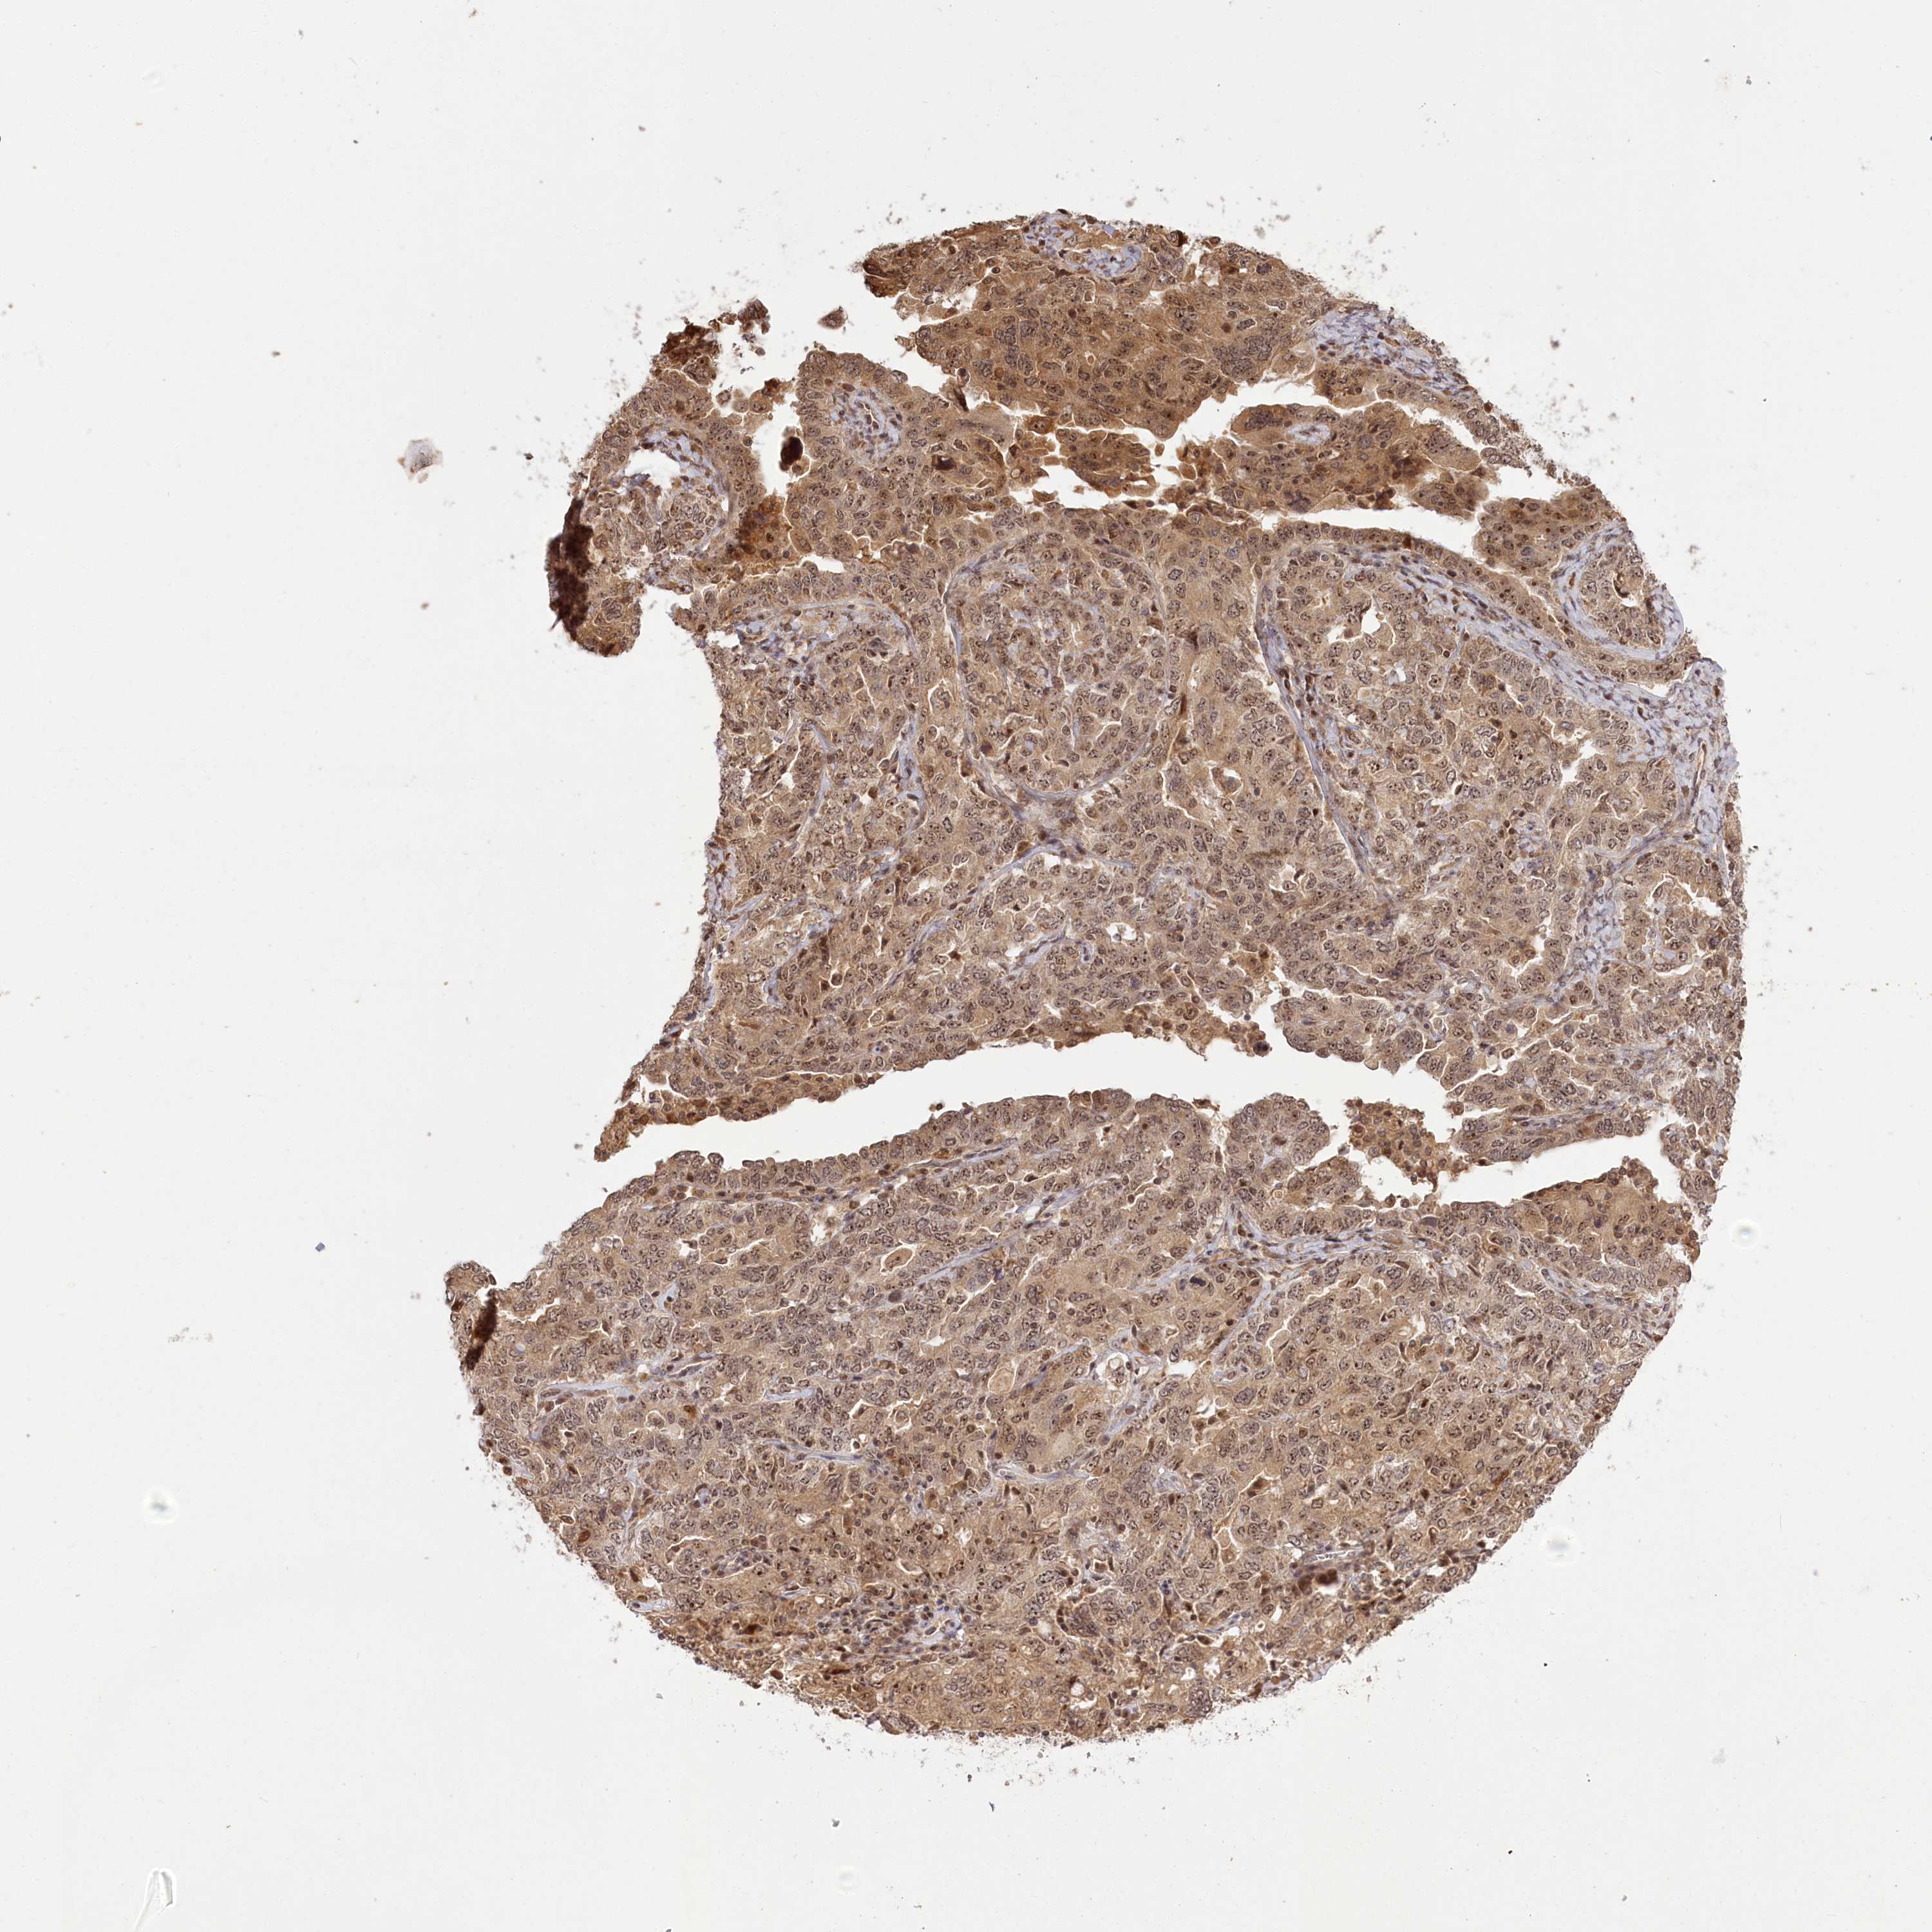

OVARIAN CANCER - Protein expressioni

A mouse-over function shows sample information and annotation data. Click on an image to view it in a full screen mode. Samples can be filtered based on level of antibody staining by selecting one or several of the following categories: high, medium, low and not detected. The assay and annotation is described here.

Note that samples used for immunohistochemistry by the Human Protein Atlas do not correspond to samples in the TCGA dataset.

Antibody stainingi

Antibody staining in the annotated cell types in the current human tissue is reported as not detected, low, medium, or high, based on conventional immunohistochemistry profiling in selected tissues. This score is based on the combination of the staining intensity and fraction of stained cells.

Each image is clickable and will lead to virtual microscopy that enables deeper exploration of all samples and also displays staining intensity scores, fraction scores and subcellular localization as well as patient and tissue information for each sample.

Antibody HPA037811

Antibody HPA037812

Staining

High

Medium

Low

Not detected

Intensity

Strong

Moderate

Weak

Negative

Quantity

>75%

75%-25%

<25%

None

Location

Nuclear

Cytoplasmic/membranous

Cytoplasmic/membranous,nuclear

Cystadenocarcinoma, serous, NOS